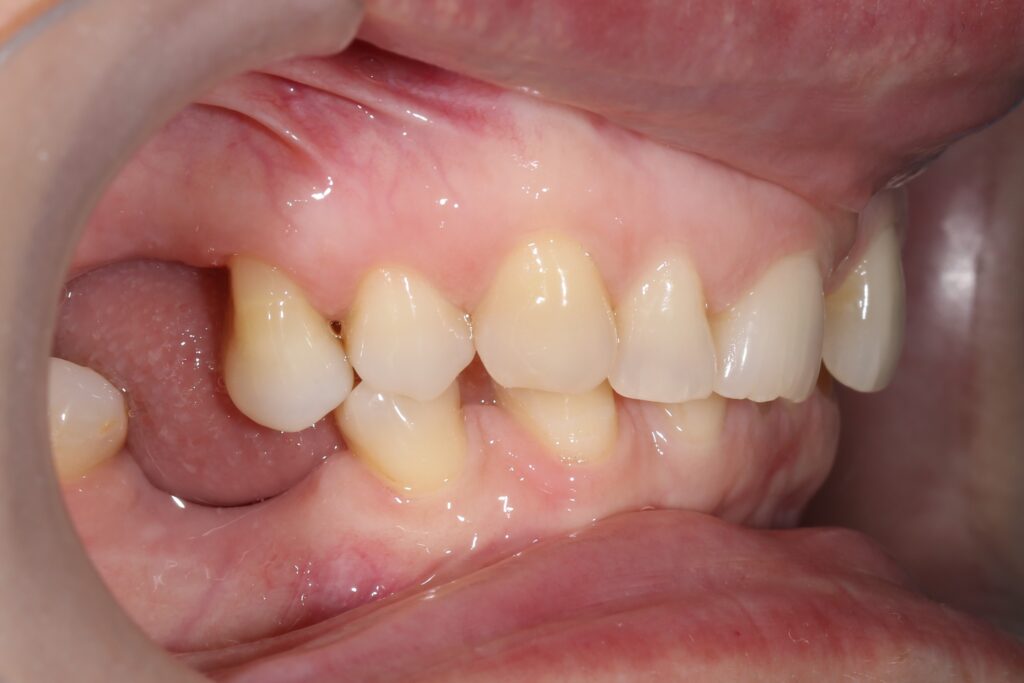

Результаты ортодонтической части

Была установлена брекет-система Damon Q. Срок лечения брекетами составил 11 месяцев.